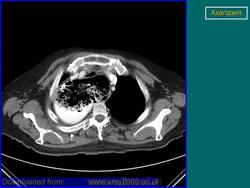

Ахалазия

Случай 13: ахалазия, имитирующая медиастинальную массу

Ахалазия имитирует объёмный процесс в средостении.